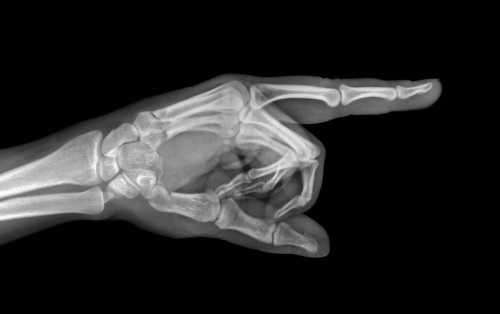

СНИМОК КИСТИ В БОКОВОЙ ПРОЕКЦИИ

Назначение снимка. Снимок кисти в боковой проекции сравнительно мало информативен, так как II—V пястные кости и фаланги II—V пальцев проекционно наслаиваются друг на друга; изолированно видны лишь I пястная кость и фаланги I пальца. Поэтому в практической работе боковой снимок кисти часто заменяют снимком кисти в косой проекции.

Укладка больного для выполнения снимка. Кисть прилежит к кассете ульнарным краем. Пальцы выпрямлены и сомкнуты.

Плоскость ладони перпендикулярна плоскости кассеты. Пучок рентгеновского излучения направлен в проекции головок пястных костей в центр кассеты (рис. 369).

Информативность снимка. Снимок используют в травматологии как дополнительный снимок для определения смещения отломков пястных костей (рис. 370).